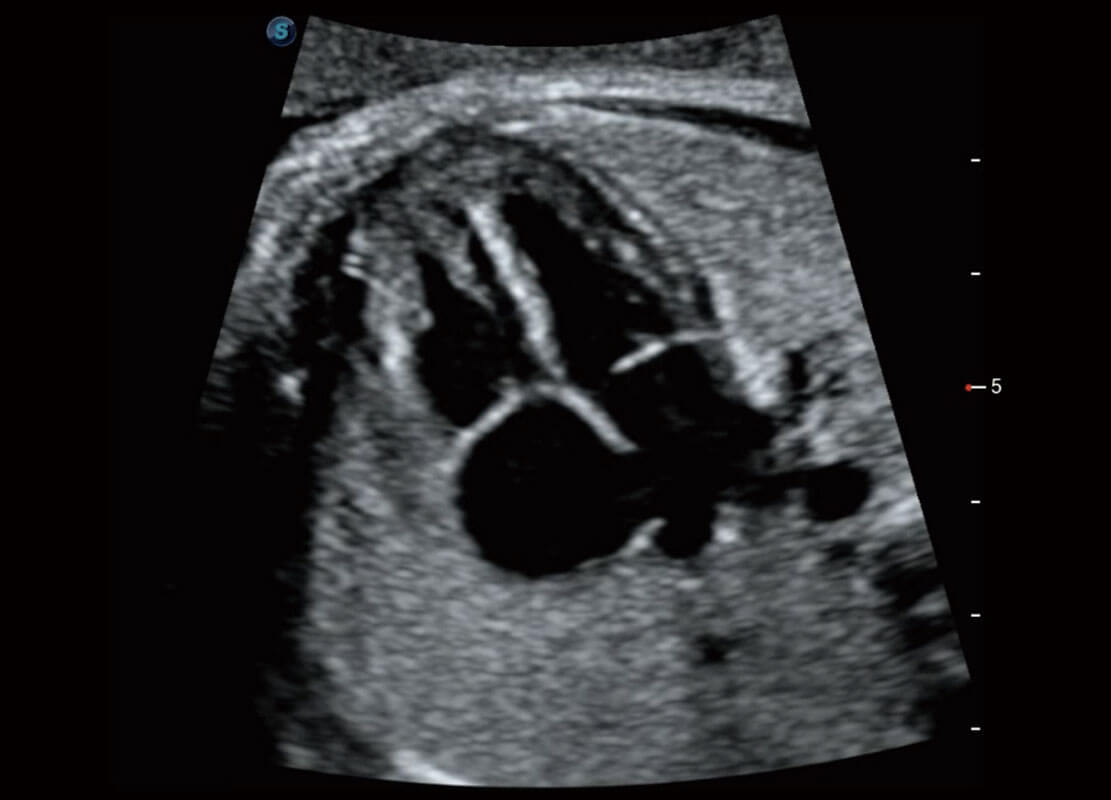

P60搭载一系列胎儿心脏成像技术,实现精细的胎儿心脏评估。

四腔切面

右室双出口